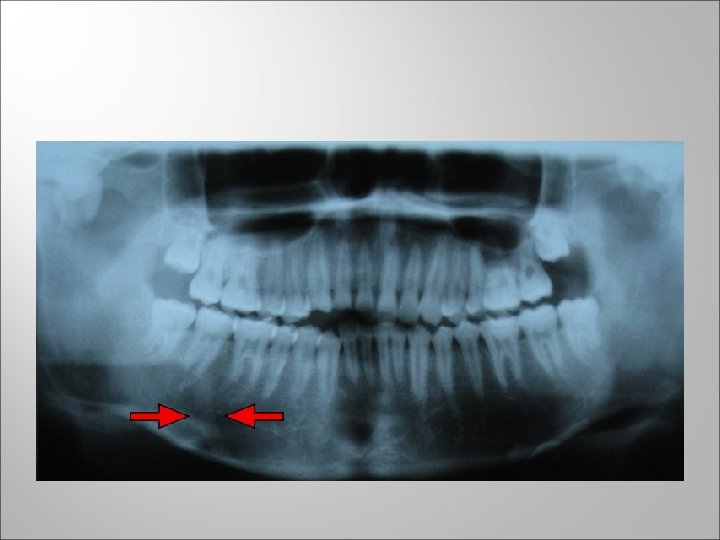

Osteoradionecrosis q q q Is not primarily an infectious process, it is exposure of bone within radiation treatment volume of 3 months or longer in duration. It may progress to intractable pain and pathological fracture of mandible, often accompanied by orocutaneous fistula and requiring resection of major portion of mandible. The dose to bone is probably the best predictor of risk.

In a study by Morrish, in which dose to bone was calculated on all patients, mandibular bone necrosis developed in 85% of dentulous patients who received 7500 c. Gy or more to bone. None of the patients who received less than 6500 c. Gy to mandibular bone develop necrosis.